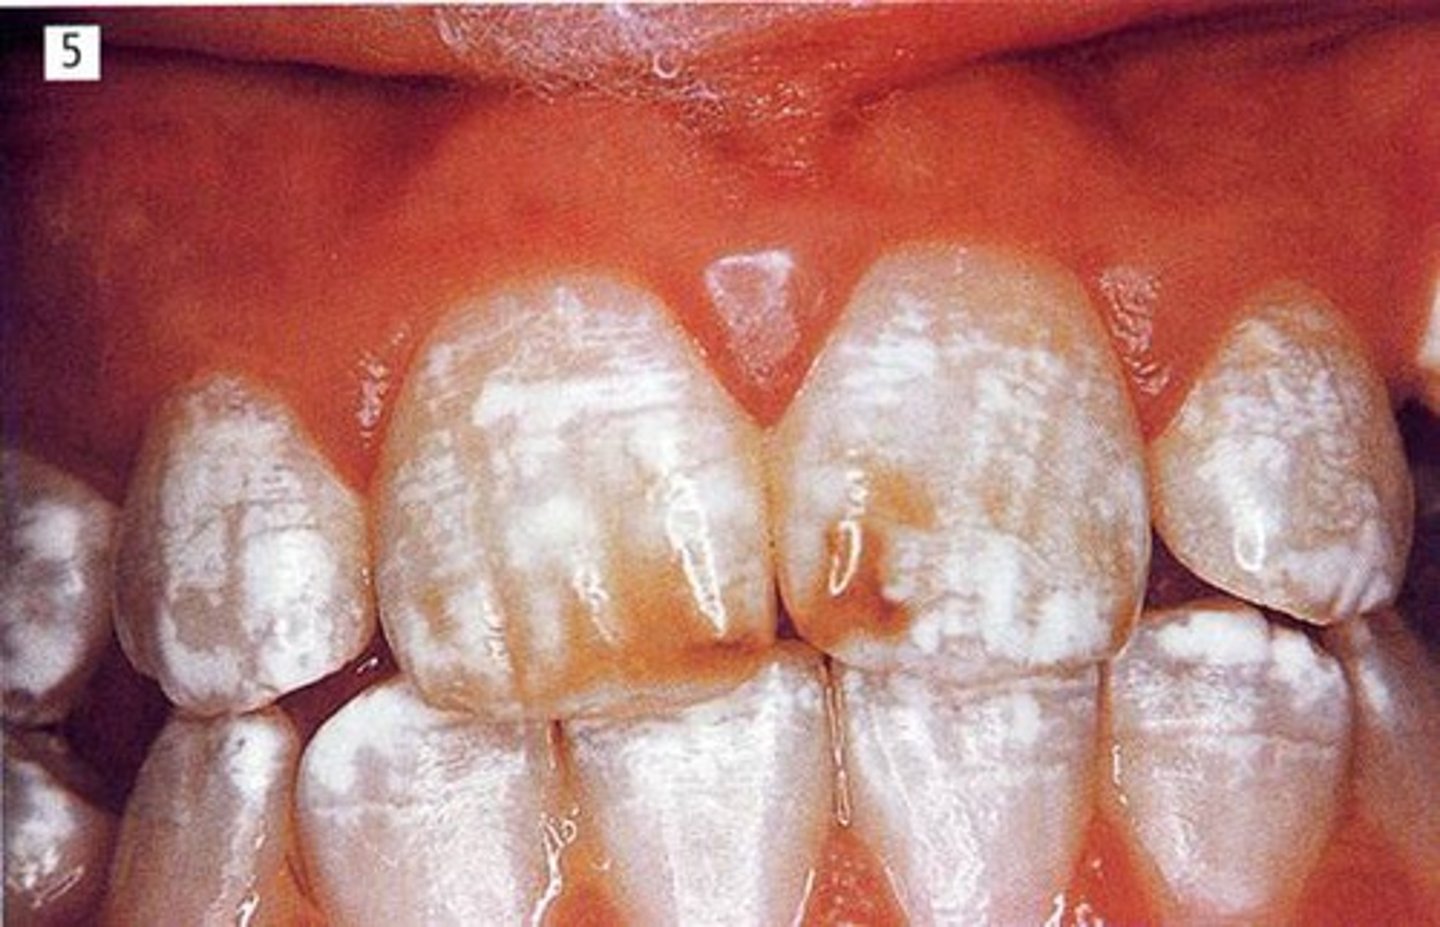

looks like white and brown spots on the teeth

hypocalcified teeth

___ cannot be reversed

but microabrainsion and aching can improve aesthetics, but cannot reverse the condition

fluorosis

flurosis can be caued by a patient living in a region wher the fluoride content in the water is ____ppm. Normal is ____ppm

4ppm

normal is 0.7ppm